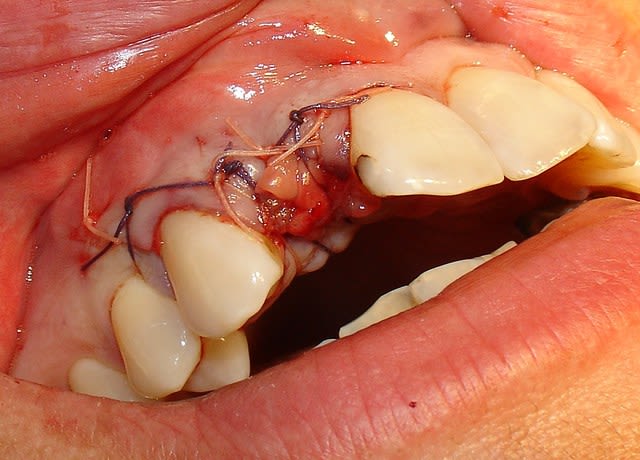

juste pour illustrer mon propos....

ici une MCI ou plutôt, devrais je dire une vis de cica anatomique immédiate.